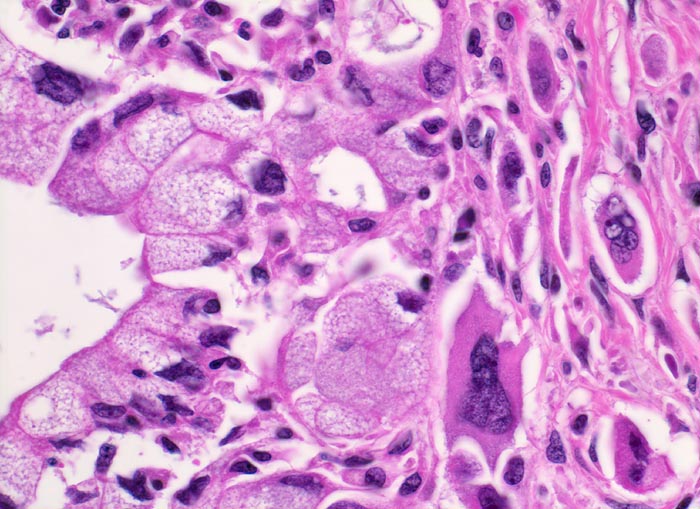

Die meisten Pankreaskarzinome sind mässig bis hoch differenziert und führen zu einer deutlichen desmoplastischen Stromareaktion (derbe Konsistenz). Hochdifferenzierte Tumoren (> 1502) können sehr ähnlich aussehen wie eine chronische Pankreatitis (> 4243). Im Gegensatz zur Pankreatitis sind die neoplastischen Drüsen verformt oder rupturiert und zeigen zelluläre Atypien (grosse polymorphe Kerne mit prominenten Nucleolen). Die Tumordrüsen sind unregelmässig im Stroma angeordnet und nicht lobulär wie in der Pankreatitis. Nicht selten ist eine Nervenscheideninvasion nachweisbar (> 5884). Gelegentlich zeigen die Gänge im tumorfreien Parenchym dysplastische Veränderungen oder der Tumor breitet sich intraduktal entlang des Pankreasganges aus.

• Unregelmässige Anordnung der Drüsen (keine Läppchenarchitektur erkennbar).

• Kribriforme Drüsenformationen.

• Inkomplette Drüsen mit unvollständigen Lumina und Infiltration des Stromas durch Tumoreinzelzellen.

• Nekrotische Tumorzellen in den Drüsenlumina.

• Ausgeprägte Polymorphie und Hyperchromasie der Tumorzellkerne.

• Desmoplastisches Stroma.

• Rechts oben Reste von nicht neoplastischem Pankreasparenchym mit fokaler chronisch obstruktiver Pankreatitis als Folge von tumorbedingten Gangobstruktionen: Vollständige Atrophie des exokrinen Pankreas bei erhaltenen Inseln. Ersatz des atrophen Parenchyms durch Fibrose. Chronisches Entzündungsinfiltrat.